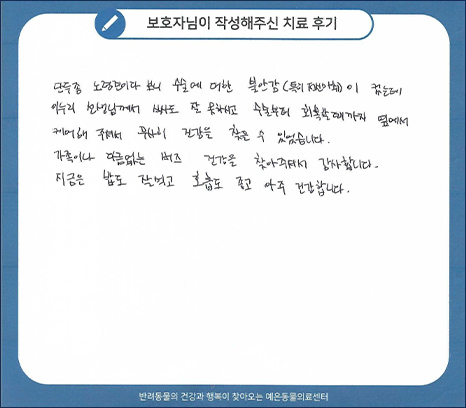

치료 후기 01

단두종 노령견이다 보니 수술에 대한 불안감(특히 전신마취)이 컸는데 이누리 선생님께서

식사도 잘 못하시고 수술부터 회복할 때까지 옆에서 케어해 주셔서 무사히 건강을 찾을 수 있었습니다.

가족이나 다름없는 버즈 건강을 찾아주셔서 감사합니다.

지금도 밥도 잘먹고 호흡도 좋고 아주 건강합니다.